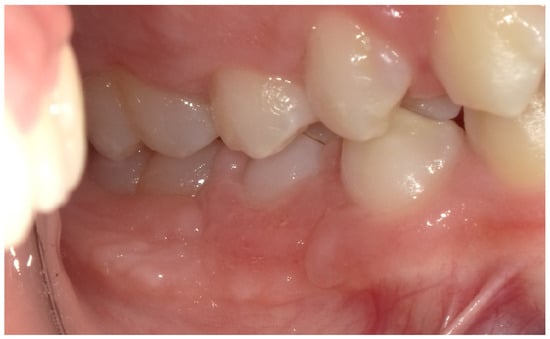

2.5. Follow-Up and Outcomes

3. Results